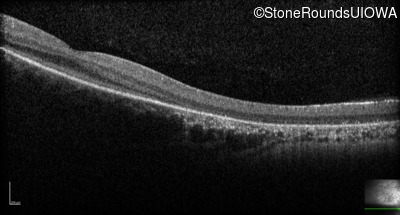

Optical Coherence Tomography - Right - No Light Perception

Exemplar / OCT Stack